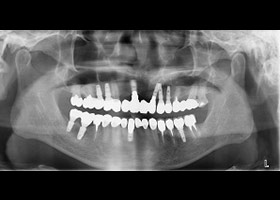

治療前

多顆缺牙及牙周病、蛀牙

proimages/Case/dentalimplant/10/02/before01.jpg

proimages/Case/dentalimplant/10/02/before02.jpg

proimages/Case/dentalimplant/10/02/before03.jpg